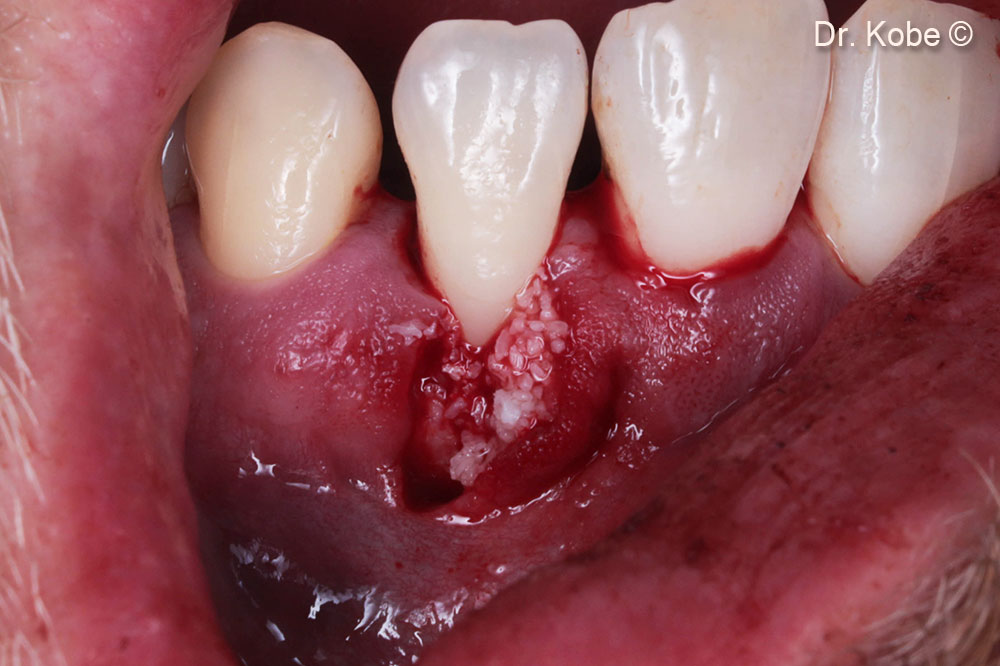

Access to the defect

Defect filled with Gen-Os®